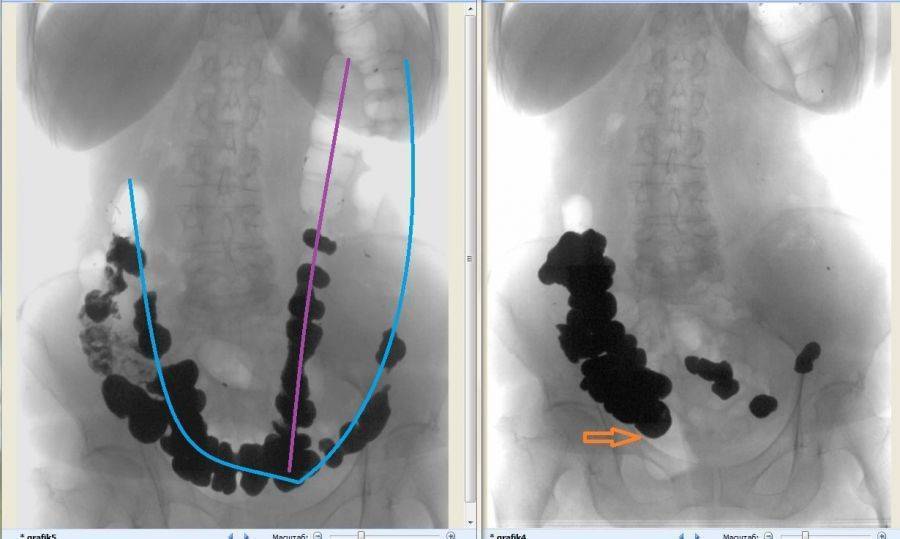

Обязательно больному предстоит пройти ирригографию, которая позволяет обнаружить количество и степень завитков кишки.

Ректальное обследование позволяет обнаружить незаполненную ампулу прямой кишки. Значит, выше имеются причины, затрудняющие прохождение кала. Рентгеновское исследование проводится путем предварительного приема внутрь бариевой взвеси или непосредственным введением контрастного вещества в кишку с клизмой (ирригоскопия).

При поступлении с питьем врач в первый день имеет возможность осмотреть пищевод, двенадцатиперстную кишку и состояние желудка. На второй день контраст должен заполнить петли толстой кишки. При рентгеноскопии выявляют: опущение кишечника (колоноптоз), задержку контраста в зоне нисходящего и сигмовидного отделов кишечника, дополнительные петли и удлинение сигмы.

Ирригография кишки проводится сразу после клизмы